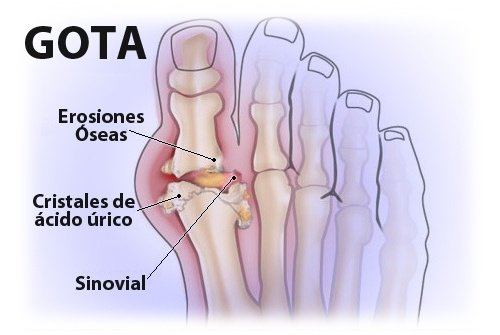

En definitiva, las causas que provocan este trastorno son muy diversas y es preciso controlarlas todas para que las desviaciones sean lo menos trascendentes posibles. Los niveles altos de ácido úrico no son fáciles de combatir, sin embargo tampoco resulta imposible rebajarlos y para ello es preciso realizar cambios sustanciales en nuestro día a día. Se trata de un proceso muy similar al de perder peso, que requiere constancia y esfuerzo diario. Muchas veces es necesario comenzar a notar los síntomas, como la dolorosa gota o los incómodos cálculos renales, para comenzar a actuar. Sin embargo, en dicho punto disminuir la tasa de urea en sangre será doblemente trabajoso y es preciso concienciar a la población de dicha situación.